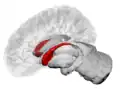

Caudate nucleus highlighted in green on sagittal T1 MRI images